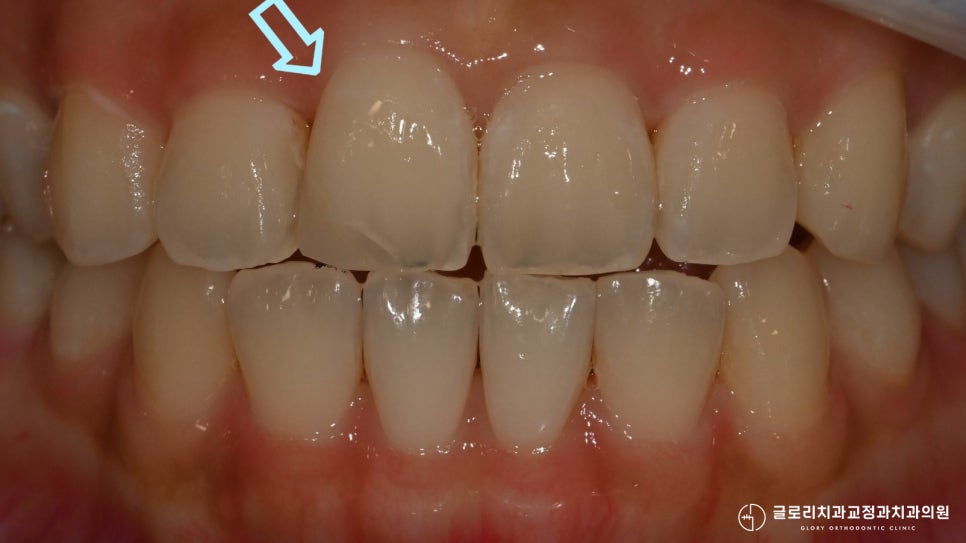

틀어진 앞니가 제자리를 찾아 배열되었으며

전체적으로 봤을 때 훨씬 긴밀하고

고르게 바뀐 것을 확인할 수 있었습니다.

고정식 유지 장치를 부착하여

틀어짐, 이동을 막아드리며

망우동치과 의 모든 과정을 마칠 수 있었습니다.